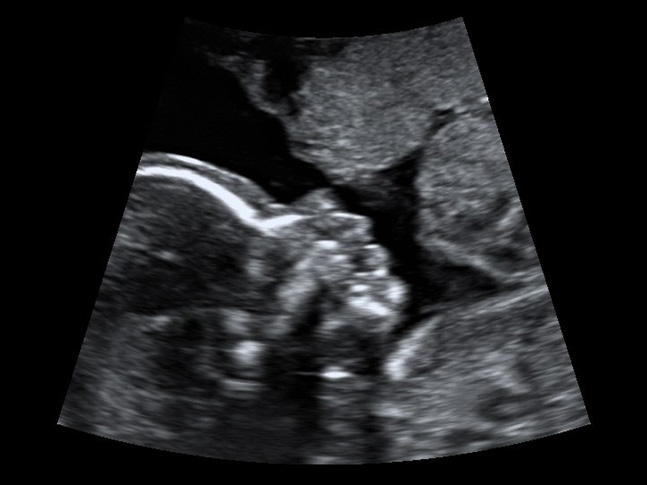

Das Ersttrimesterscreening ist eine Ultraschalluntersuchung zur Risikoberechnung für kindliche Chromosomenstörungen (Trisomie 21,13,18).

Durch Messung der Nackenfalte kombiniert mit Markern aus mütterlichem Blut (combined test) wird die statistische Wahrscheinlichkeit für das Vorliegen einer Chromosomenabweichung berechnet.

Mit einer hochauflösenden Ultraschalluntersuchung werden in der 20. bis 24. Schwangerschaftswoche das Wachstum und die Organentwicklung des ungeborenen Kindes beurteilt. Zu diesem Zeitpunkt sind die meisten vorgeburtlich diagnostizierbaren Fehlbildungen schon darstellbar.

Zu den Organen, deren Entwicklung und Struktur beurteilt wird, gehören Kopf, Gesicht, Gehirn, Hals, Wirbelsäule, Arme und Beine, Hände und Füße, Bauch und Bauchwand, Zwerchfell, Magen-Darmtrakt, Nieren und ableitende Harnwege, Herz (Echokardiografie) und – wenn erwünscht – das Geschlecht des Kindes.